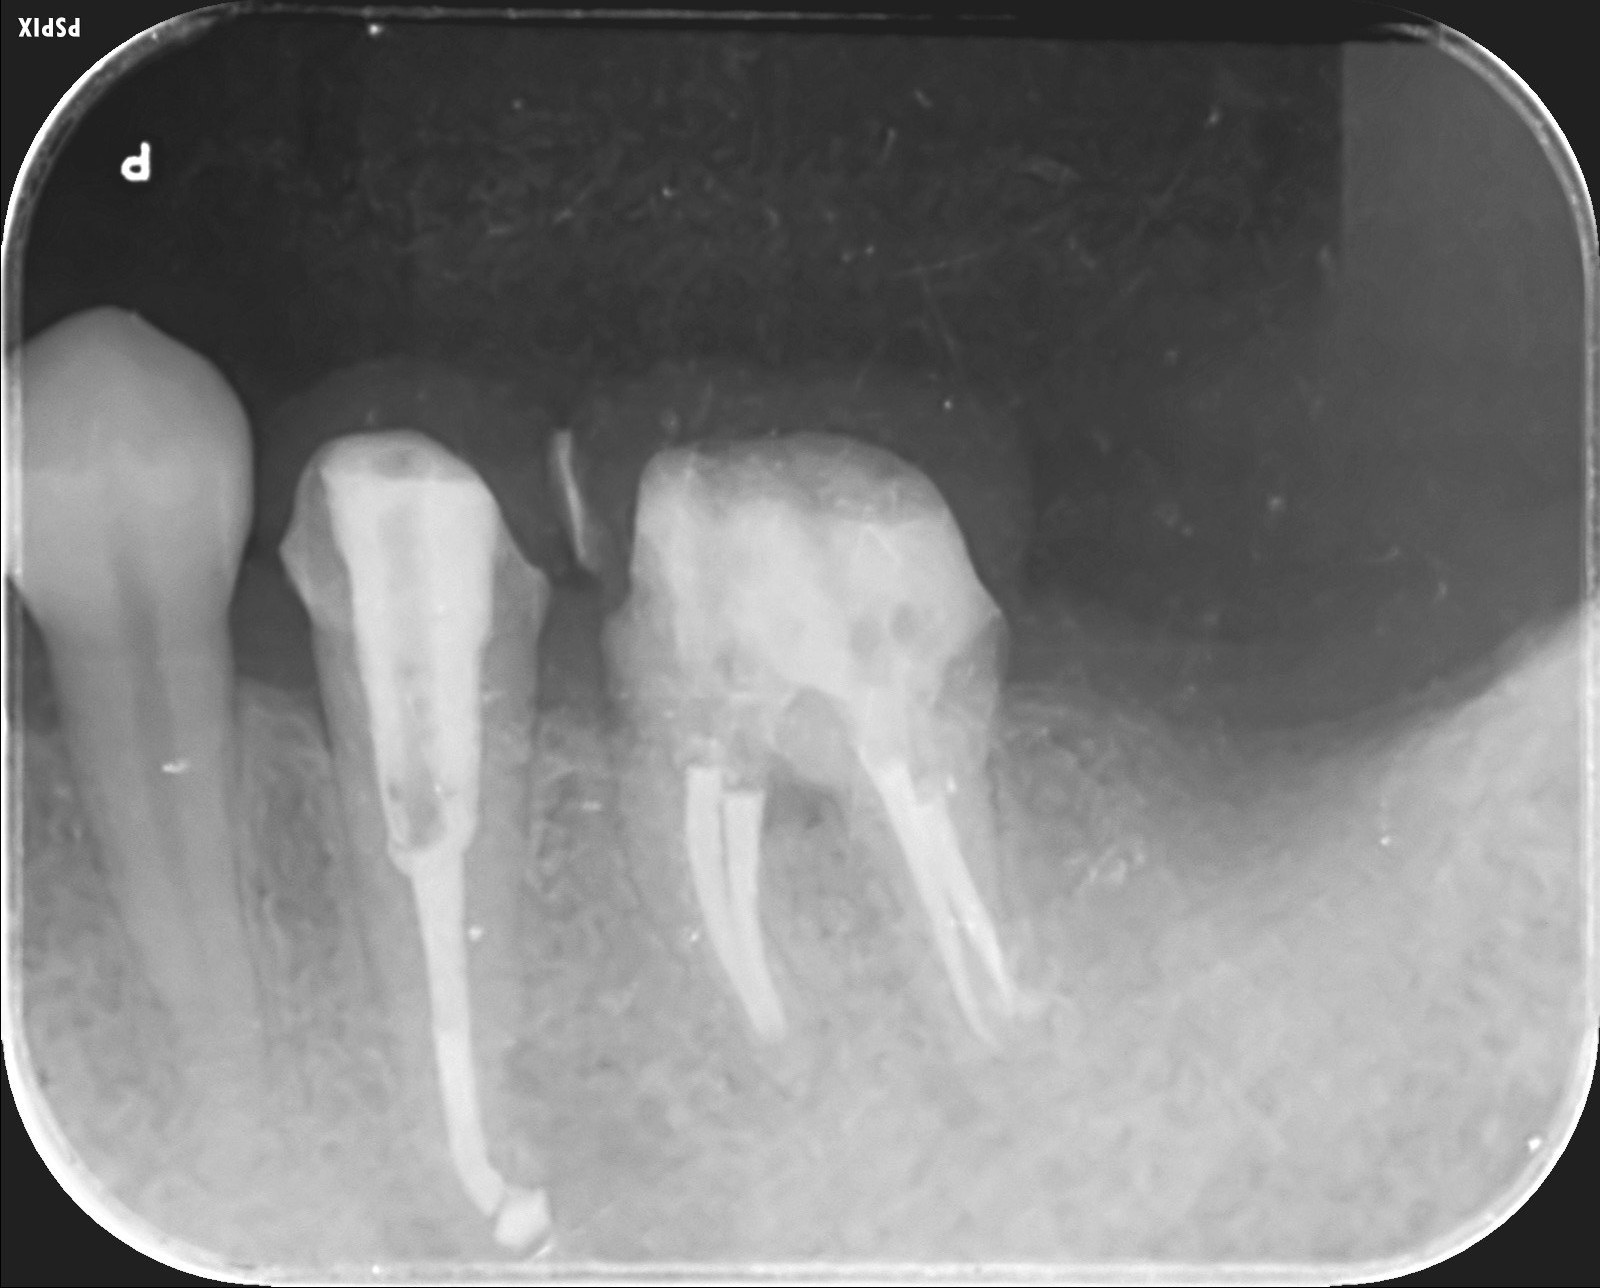

歯根破折

5番の近心側に黒い投下ぞう -

割れた歯

神経のない歯はいつ割れてもおかしくありません。 -

インプラント埋入

抜歯と同時にインプラントを埋入。インプラントと骨の隙間にはコラーゲンや骨補填材を詰めています。 -